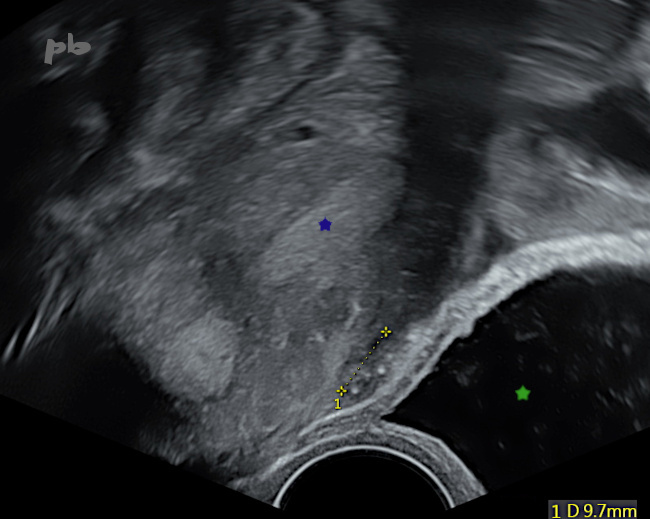

20- Adénomyose externe

Echographie endovaginale

Petite image sous-séreuse antérieure, hypoéchogène, avec piqueté hyperéchogène (entre les croix).

La paroi vésicale est respectée.

Vessie (★).

Endomètre (★).

20 – External Adenomyosis – Transvaginal Ultrasound

Small anterior subserosal image, hypo-echogenic, with hyper-echogenic speckling (between the crosses).

The bladder wall is intact.

Bladder (★).

Endometrium (★).